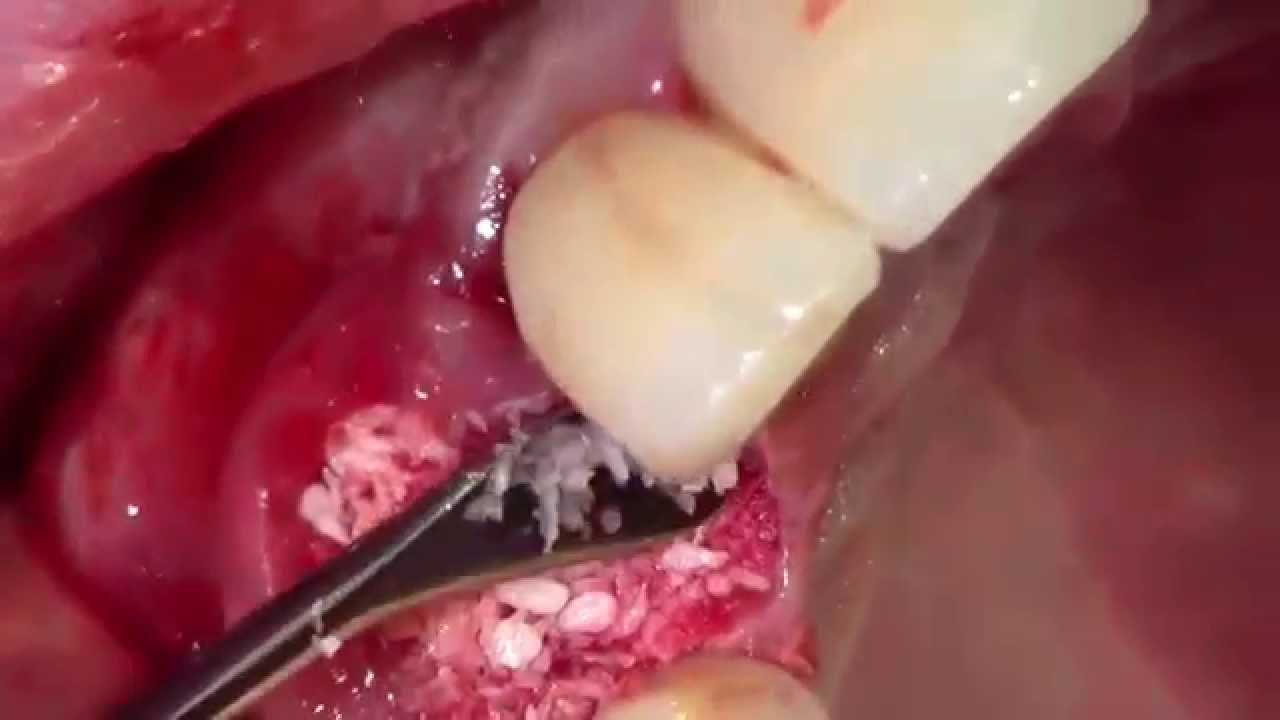

Extractions #5-12 with Simple Socket Bone Grafting (AS)